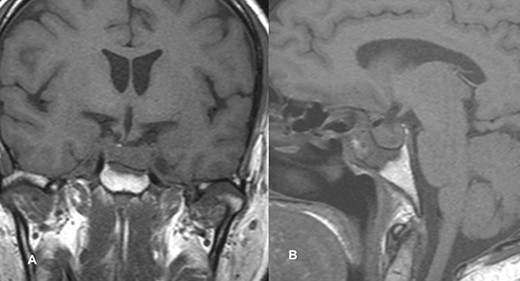

Magnetic resonance imaging (MRI) (axial T1, axial T2, coronal T1 and sagittal T1-weighted images) revealed a sellar and suprasellar lesion measuring 3 × 2.9 × 1.8 cm with patchy areas of high signal on T1-weighted images and signal void on T2-weighted images suggestive of hemorrhage. The suprasellar component of the lesion was displacing optic chiasma superiorly and the sellar component was causing sellar expansion with mass effect on bilateral cavernous sinuses (left>right); right internal carotid artery (ICA) had a contact angle of 90°, whereas left ICA had >90° (Fig. 1).

MRI images of axial T1 (A), axial T2 (B), coronal T1 (C), and sagittal T1-weighted images (D) showing a 3 cm × 2.9 cm × 1.8 cm sized suprasellar lesion displacing optic chiasma superiorly and laterally causing a mass effect on bilateral cavernous sinuses (Left>Right) with patchy areas of high signal on T1-weighted images and signal void on T2-weighted images suggestive of hemorrhage.